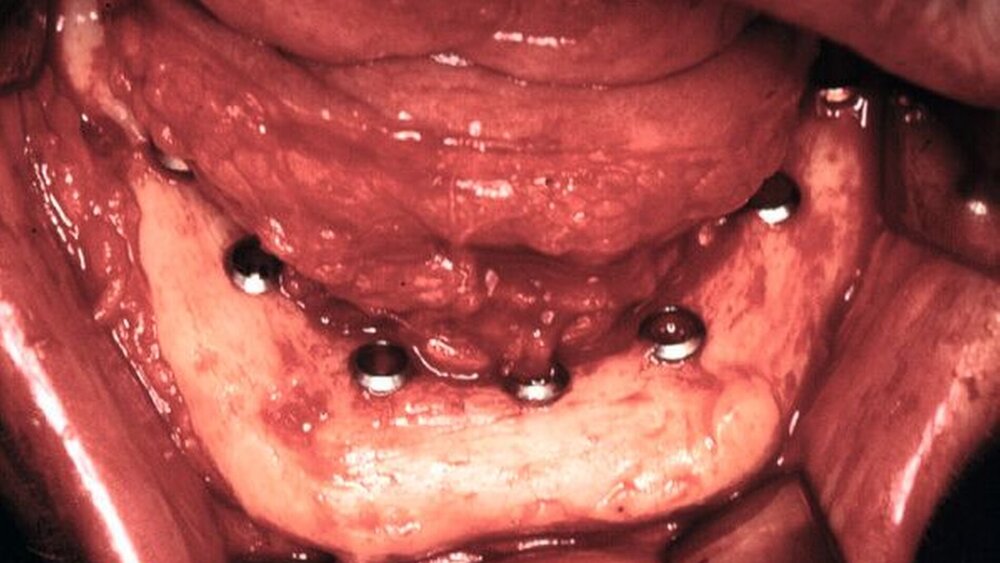

Da Patienten nach einer tumorbedingten Zahn- und/oder Kieferteilentfernung kaufunktionell behindert sind und eine signifikant geringere Lebensqualität aufweisen als prothetisch versorgte Patienten [Allison et al., 1999], ist die Organisation der dentalen Rehabilitation eine wichtige Aufgabe der Tumornachsorge. Die prothetische Versorgung kann dabei aufgrund der postoperativ veränderten Anatomie problematisch sein und erfordert nicht selten ein besonderes Engagement des Behandlers. Obwohl die Insertion dentaler Implantate in den verbliebenen Kieferknochen oder in mikrovaskulär anastomosierte Knochentransplantate zu einer erheblichen Erweiterung der prothe- tischen Möglichkeiten geführt hat, muss mit einer erhöhten Implantat-Verlustrate im bestrahlten Knochen – besonders bei Rauchern – gerechnet werden [Mericske-Stern et al., 1999]. Es gibt keine ausreichende Evidenz für ein am besten geeignetes prothetisches Vorgehen bei Patienten, die wegen eines Mundhöhlenkarzinoms operiert und/oder bestrahlt worden sind [McCord et al., 2004]. Zur Frage der Implantatversorgung nach Bestrahlung der Kopf-Hals-Region wird auf die S3-Leitlinie „Implantat-Versorgung zur oralen Rehabilitation in Zusammenhang mit Kopf-Hals-Bestrahlung“ (AWMF 007–089) verwiesen